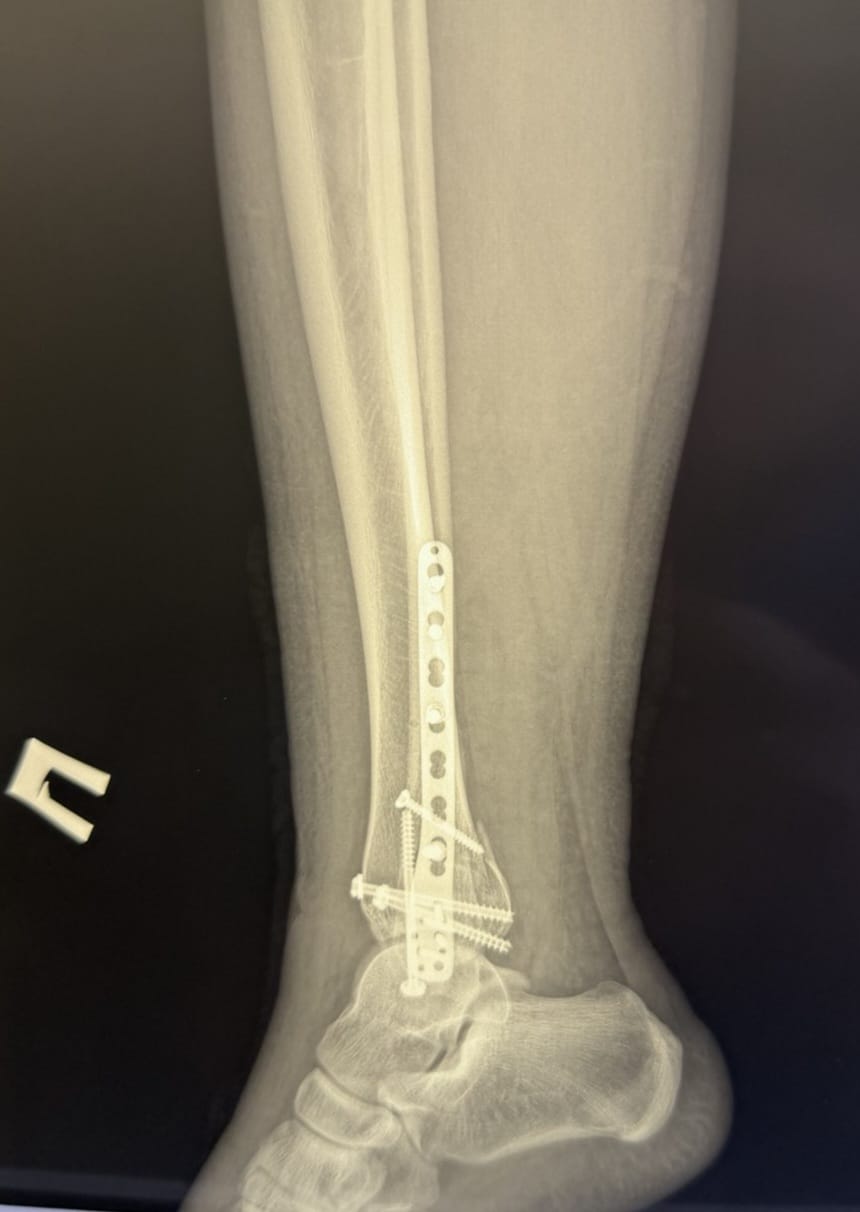

- закритий перелом правої малогомілкової кістки у нижній третині зі зміщенням;

- закритий перелом медіальної кісточки правої великогомілкової кістки зі зміщенням;

- закритий перелом заднього краю дистального відділу правої великогомілкової кістки зі зміщенням.

- відкрите зіставлення уламків правої малогомілкової кістки та остеосинтез пластиною і гвинтами;

- репозицію переломів медіальної кісточки та заднього краю дистального відділу великогомілкової кістки з фіксацією гвинтами;

- фіксацію міжгомілкового синдесмозу гвинтом для відновлення стабільності гомілковостопного суглоба.